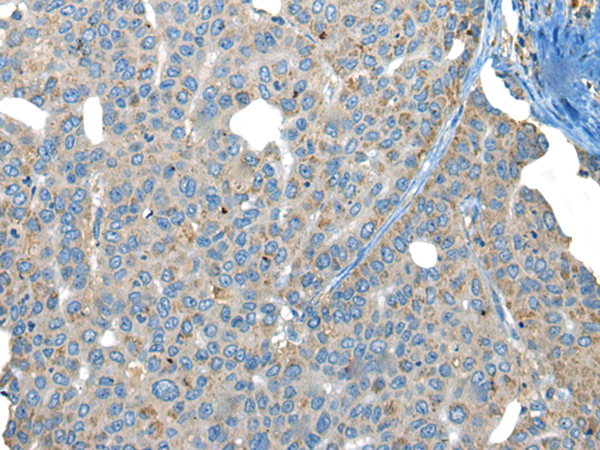

分类: 科研抗体货号: P02456别名: SHK; CARKL应用: WB,IHC反应种属: Human, Mouse

分类: 科研抗体货号: P02504别名: FHR2; HFL3; CFHL2应用: WB,IHC反应种属: Human

分类: 科研抗体货号: P02498别名: CEN3; CDC31应用: WB,IHC反应种属: Human, Mouse

分类: 科研抗体货号: P02487别名: HEPP; SEI-3/HEPP应用: WB,IHC反应种属: Human

分类: 科研抗体货号: P02561别名: ER1; MI-ER1应用: WB,IHC反应种属: Human, Mouse

分类: 科研抗体货号: P02481别名: 4F2; CD98; MDU1; 4F2HC; 4T2HC; NACAE; CD98HC应用: WB,IHC反应种属: Human

分类: 科研抗体货号: P02557别名: CRN7; POD1; 0610011B16Rik应用: WB,IHC反应种属: Human, Mouse, Rat

分类: 科研抗体货号: P02473别名: CPR4应用: WB,IHC反应种属: Human